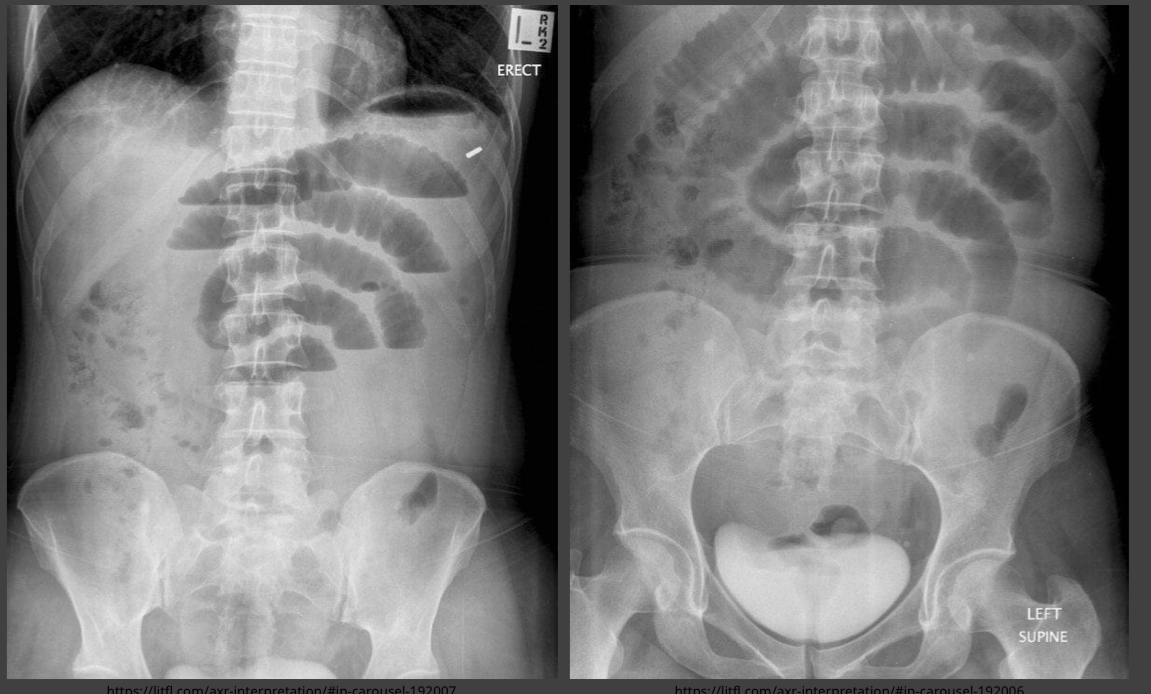

Small Bowel Obstruction

“Stacked coin” appearance.

Air-fluid levels visible on erect film.

Dilated Bowel

Indicates large bowel obstruction.